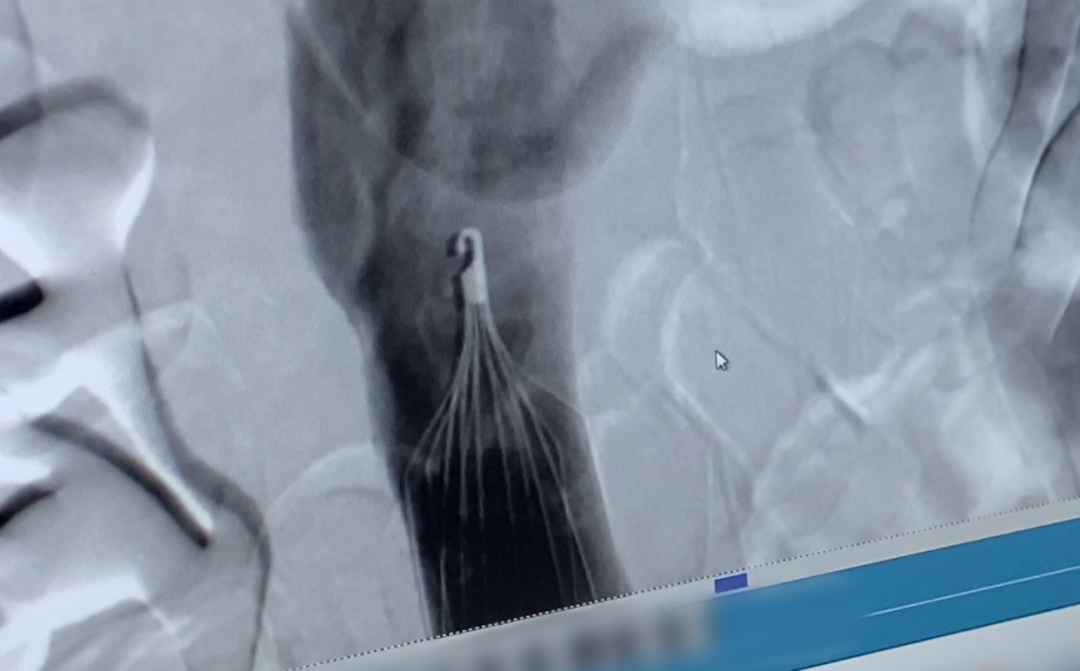

IVCF是一個金屬裝置,打開呈傘狀或梭形。經皮穿刺置入靜脈後,它像一張濾網,能攔截下肢靜脈系統脱落的血凝塊,阻止其進入肺循環,預防由此引發的致死性肺栓塞。《急性肺栓塞多學科團隊救治中國專家共識(2022)》顯示,肺栓塞是第三大心血管死亡原因,治療以抗凝和溶栓為主。對於有抗凝絕對禁忌證、經充分抗凝後仍再發肺栓塞者,可考慮置入IVCF。

楊軼表示,濾器長期置入後引發的併發症本身也會影響患者的預後。對此,張強解釋説,以前有3種濾器,第一是永久型的,放進去、取不出來。第二種是臨時濾器,到時間一定要取出來。第三種是可回收型,可以取出來,也可根據患者實際情況長期留在體內,目前在市場上佔主流。

不論哪一種濾器,置入體內時間越長,出現併發症的風險越高,包括濾器本身的遠期斷裂、移位等,以及濾器穿透下腔靜脈,導致胰腺炎、膿腫形成、十二指腸出血、主動脈損傷、輸尿管損傷和脊柱損傷等。

據美國FDA2014年建議,臨牀醫師在濾器置入後的25-54天內,需要儘早取出濾器,避免或減少滯留造成的不良事件。我國《共識2020》稱,傘形和梭形可回收濾器的窗口期分別為數天至數十天或2周。